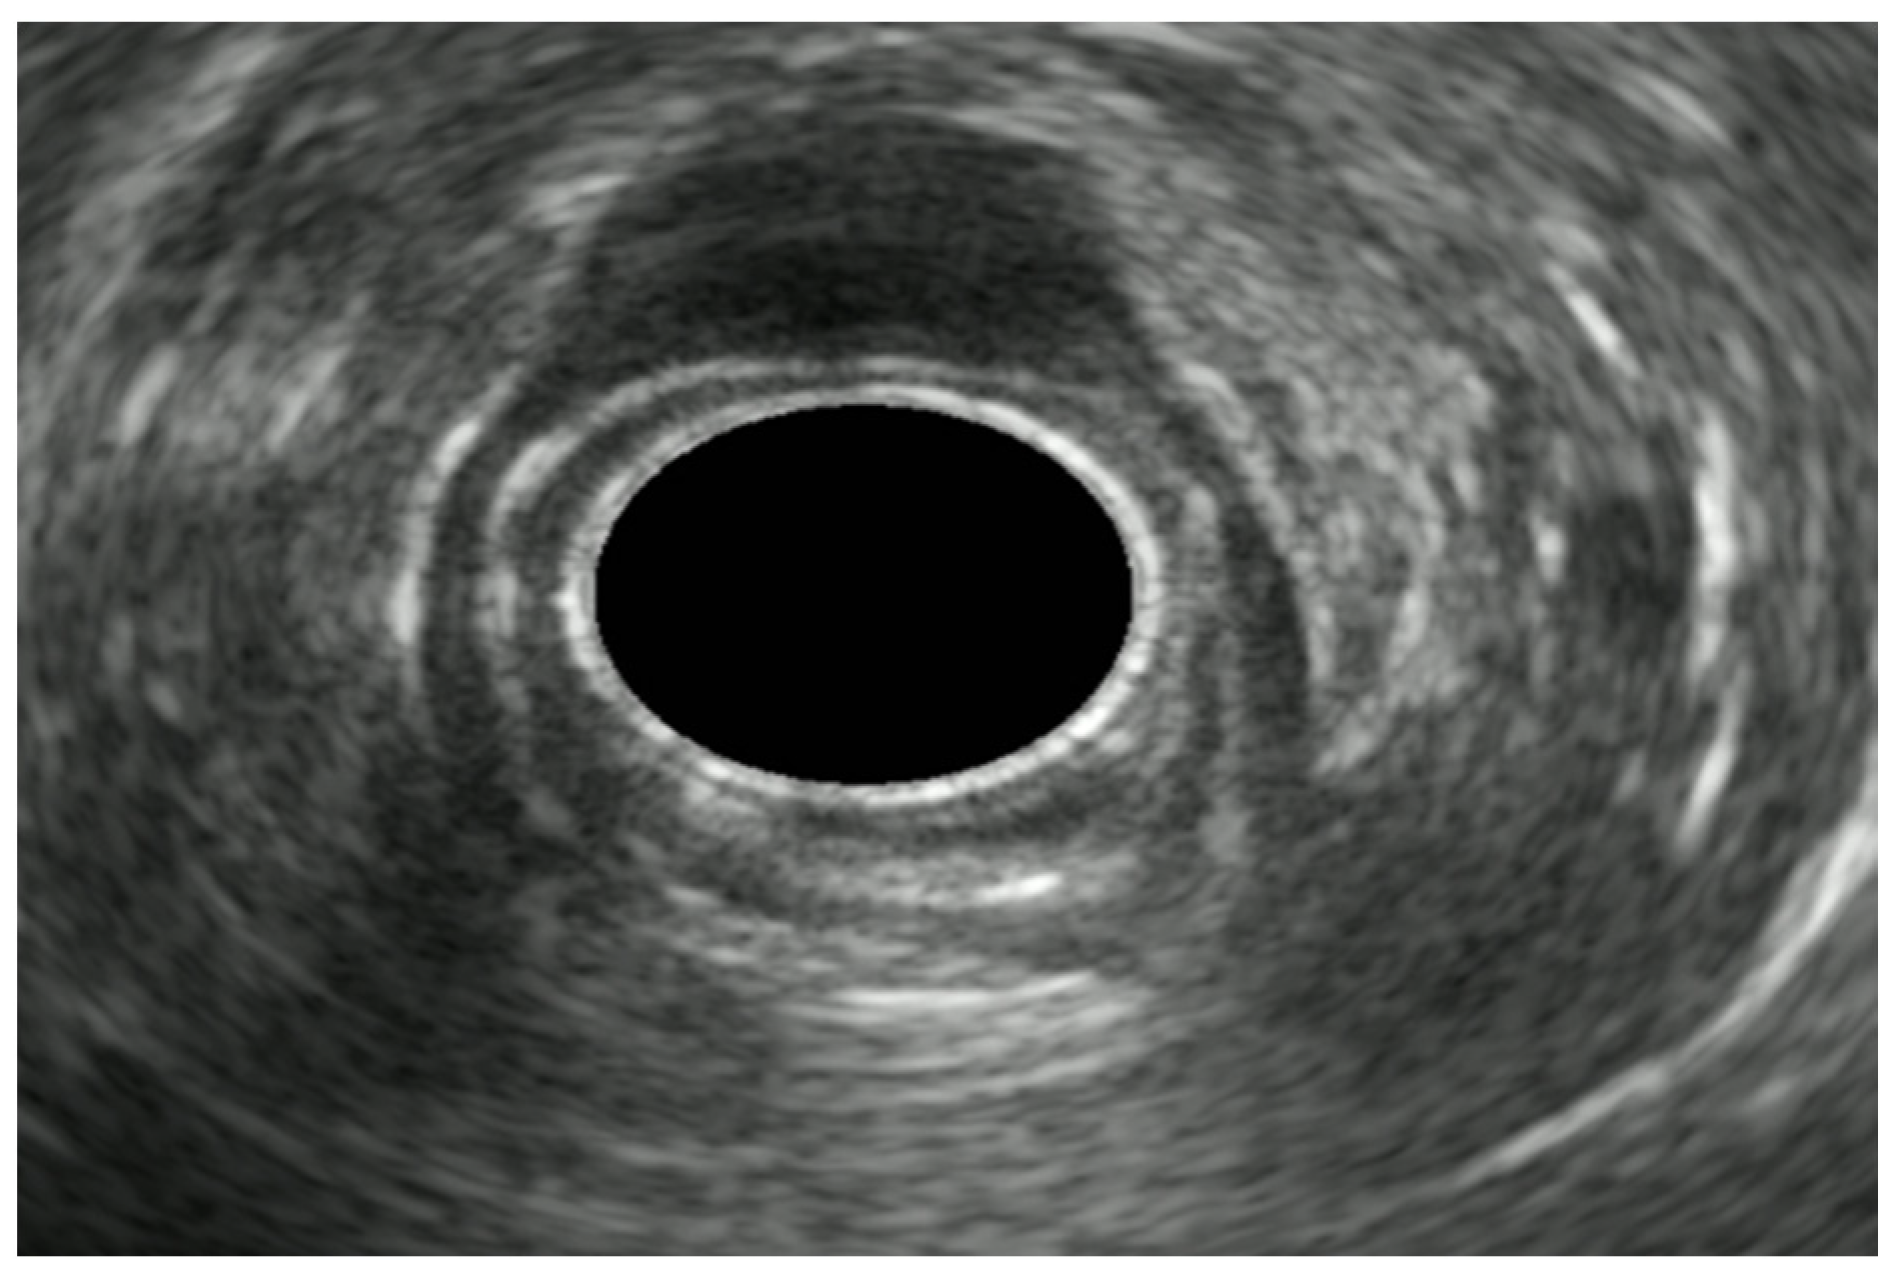

5.1.1. Esophageal Cancer

5.1.2. EUS in Superficial Esophageal Cancer

5.1.3. EUS in Advanced Esophageal Cancer

5.2. Esophageal Subepithelial Lesions